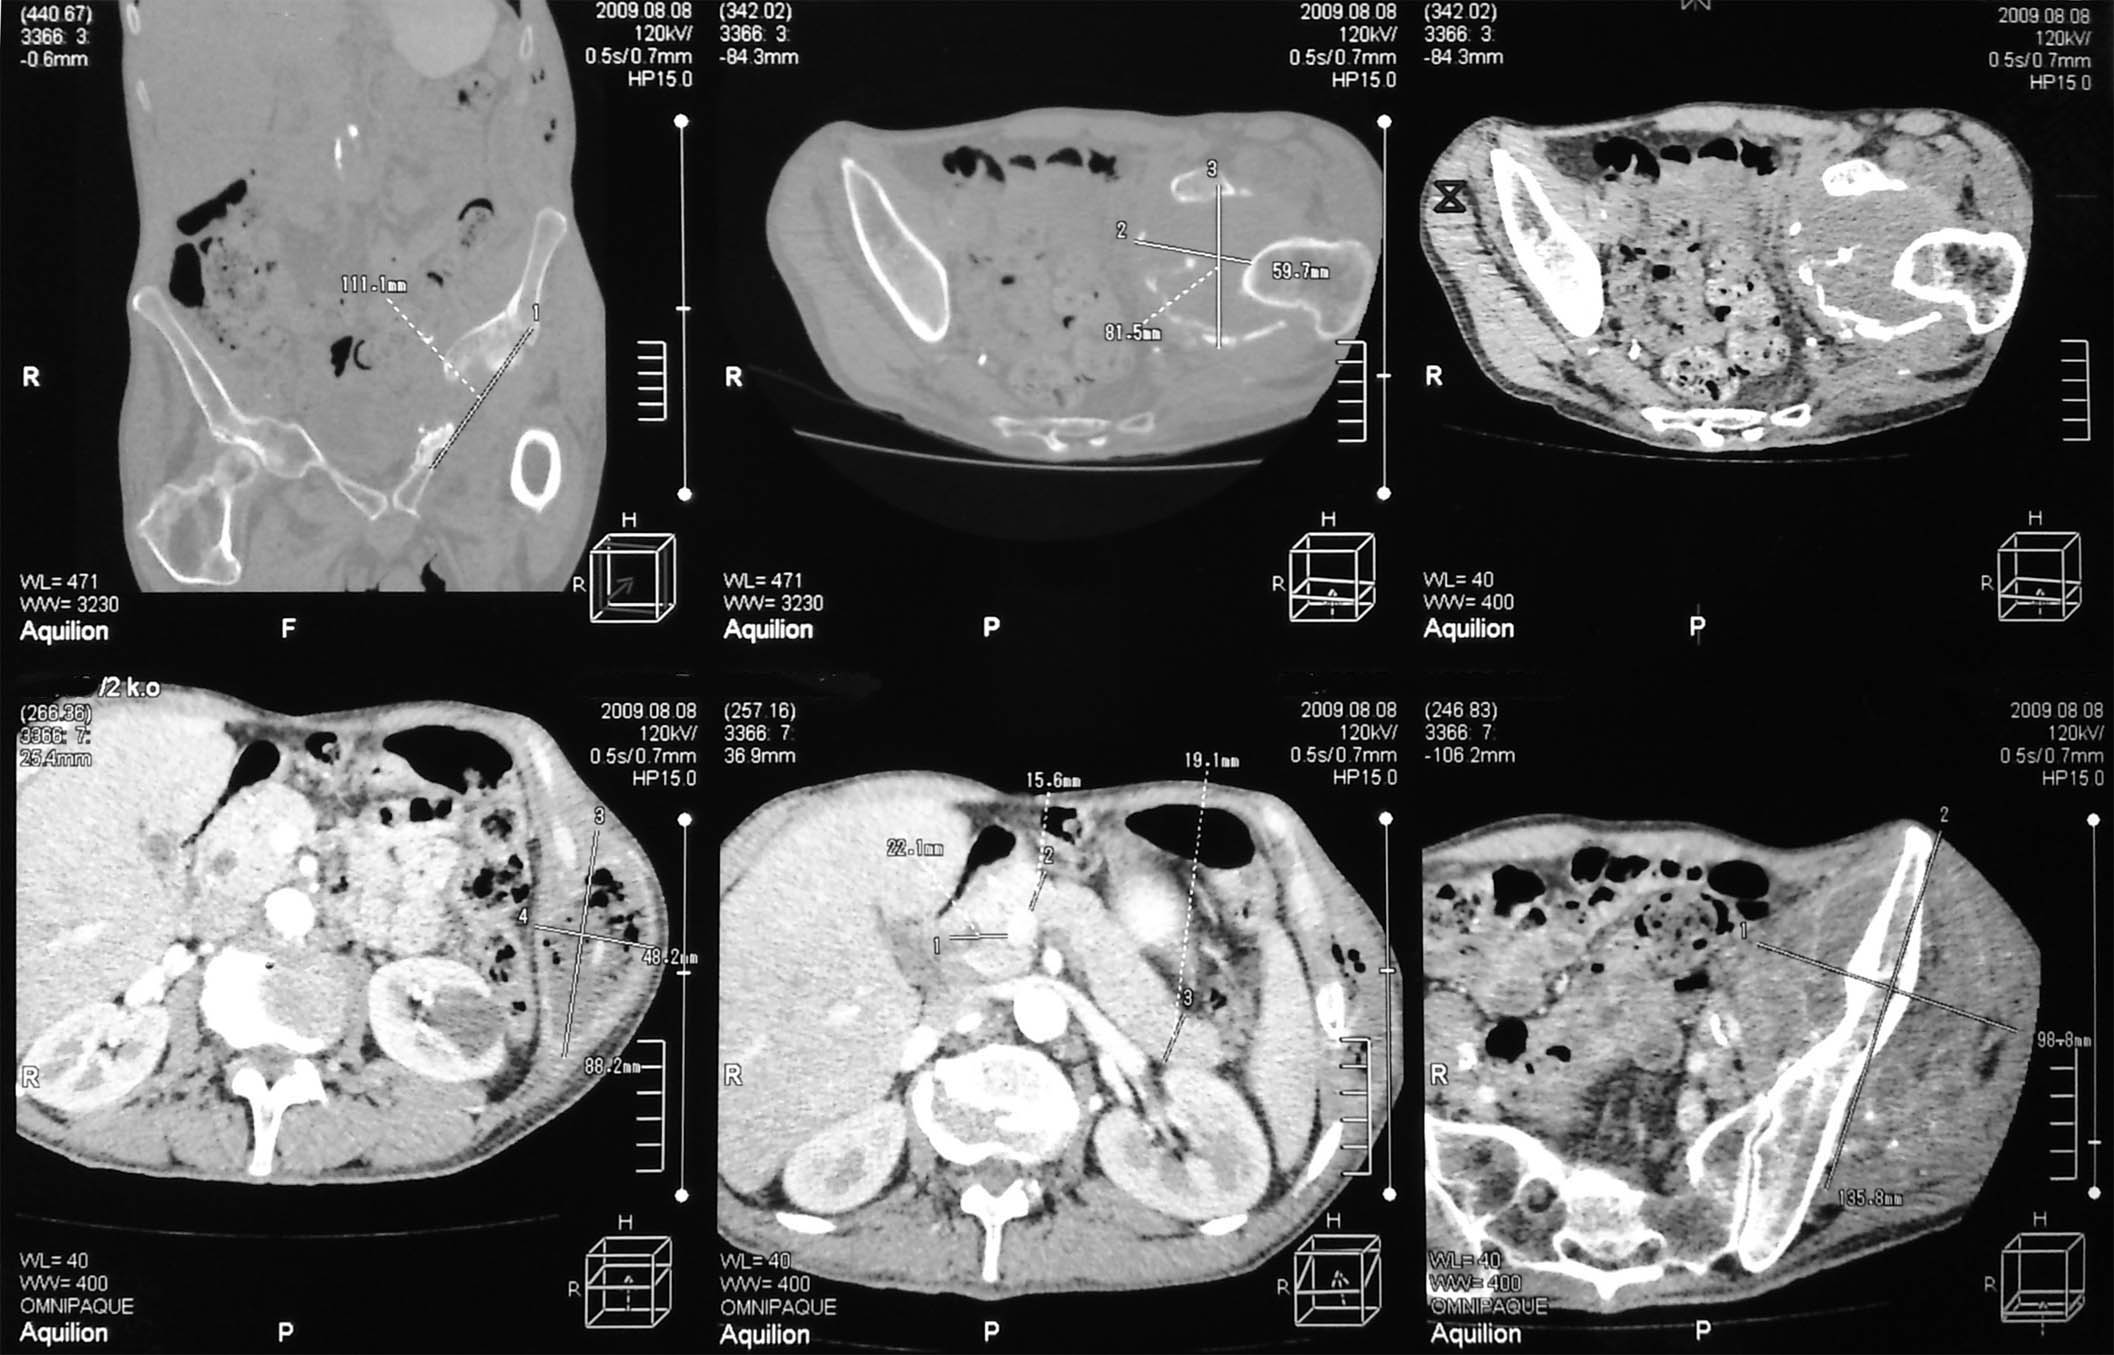

Здесь представлены КТ срезы брюшной полости и таза с контрастированием, выполненные через 2 года после травмы.

Реконструкции

на серии кт определяются в средней трети левой почки ,латерально от ее ворот определяется гиповаскулярный участок с четкими ровными контурами .с поддавливанием чашечно-лоханочной системы,ограниченый капсулой почки ,неправильной вытянутой формы ,который в поздней венозной фазе не изменяет своей визуализации (д.д между кистой и кистозной формой почечно-клеточного рака).латерально от левой почки в мягких тканях определяется большой участок со сниженной денситометрической плотностью,размерами - 53х117мм ,с включениями газа и кольцом периферического усиления,с дренажом(вероятнее всего крупный абсцесс).печень увеличена в размере,селезенка с включениями кальция .размеры поджелудочной железы в пределах нормы,холедох и вирсунгов проток без патологии.надпочечники нормальных размеров,без изменений.в области левого тазобедреного сустава определяется участок деструкции с разрушением вертлужной впадины ,головки и шейки бедренной кости ,смещением повздошной кости вверх и латерально на 111.1мм,с фрагментом головки левой бедренной кости .в левой повздошной кости определяются гиперостоз с обширным участком остеосклероза и мелкими участками остеолитической деструкции (смешанный тип).аналогичные остеолитические изменения в крыле правой повздошной кости и в головке правой бедренной кости (сужу по 3d).по медиальному контуру средней трети тела поздошной кости определяется разрушение замыкательной пластинки с вовлечением губчатого вещества на большом протяжении,в крыше и самой вертлужной впадине с мягкотканным компонентом ,с участками пониженной денситометричской плотности (вероятнее всего участки некроза),с мелкими костными фрагментами (что косвенно может подтверждать рост изнутри снаружу),с поддавливанием на большом протяжении органов малого таза,латерально -левая стенка мочевого пузыря утолщена.вывод :такие изменения могут быть как первичного так и метастатического характера .первопричина протрузии возможно врожденного характера(дисплазия) ,затем перелом усугубил процесс(посттравматическая протрузия).меня настораживает тот момент,что изменения в повздошной кости напоминают хронический остемиелит изначально .а затем появились изменения ,сильно напоминающие озлакочествление+изолированно крупный абсцесс